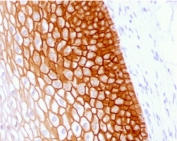

IHC testing of FFPE human tonsil with recombinant CD44v4 antibody (clone CD44v4/1700). Required HIER: steam sections in pH 9 10mM Tris with 1mM EDTA buffer for 20 min.

Applications Immunohistochemistry (FFPE) : 1-2ug/ml for 30 min at RT